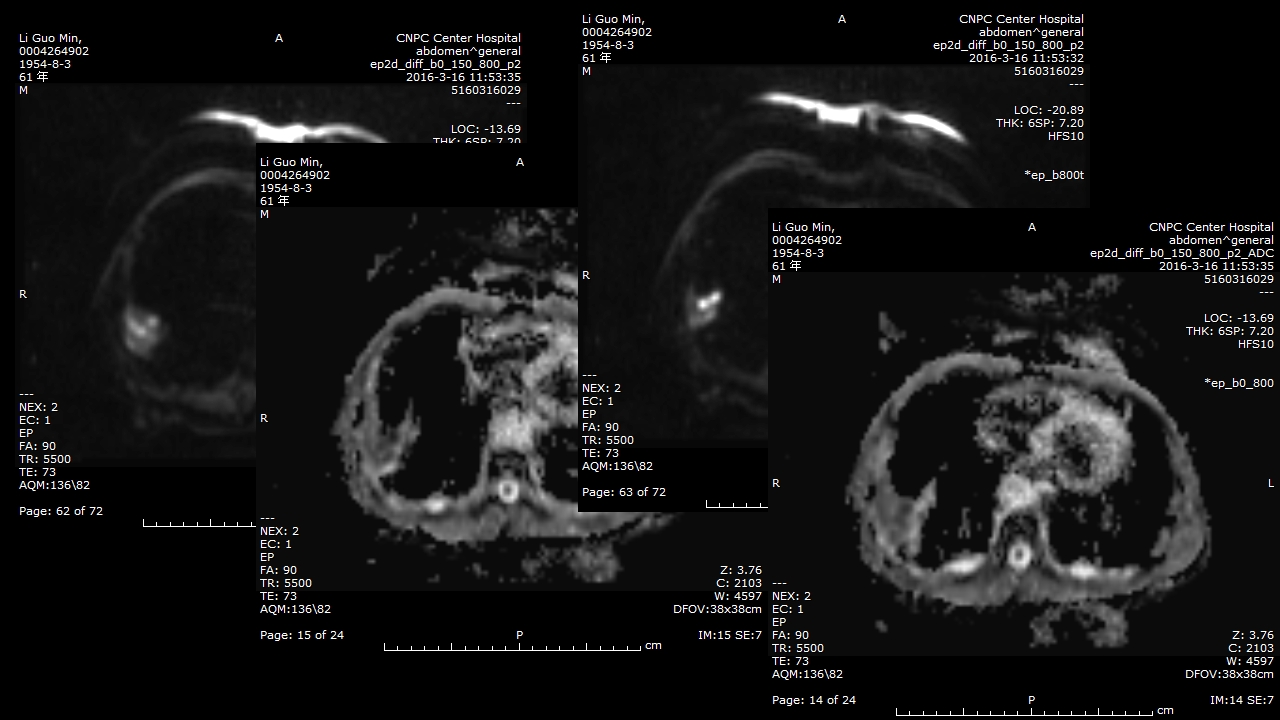

肺部肿块有效的影像检查选择